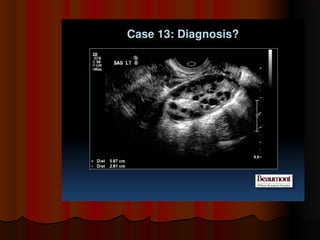

placental chorioangiomaplacental chorioangioma

 Sonography of the placenta inSonography of the placenta in

this 16 week pregnancy showsthis 16 week pregnancy shows

a large, solid mass, that is nona large, solid mass, that is non

calcific and shows mildcalcific and shows mild

vascularity (vascular) andvascularity (vascular) and

excludes placental hematomaexcludes placental hematoma..

and shows many cystic spacesand shows many cystic spaces

within itwithin it.. This tumor of theThis tumor of the

placenta lies close to the cordplacenta lies close to the cord

insertion siteinsertion site.. UltrasoundUltrasound

images of this type of placentalimages of this type of placental

mass are highly suggestive ofmass are highly suggestive of

placental chorioangiomaplacental chorioangioma..